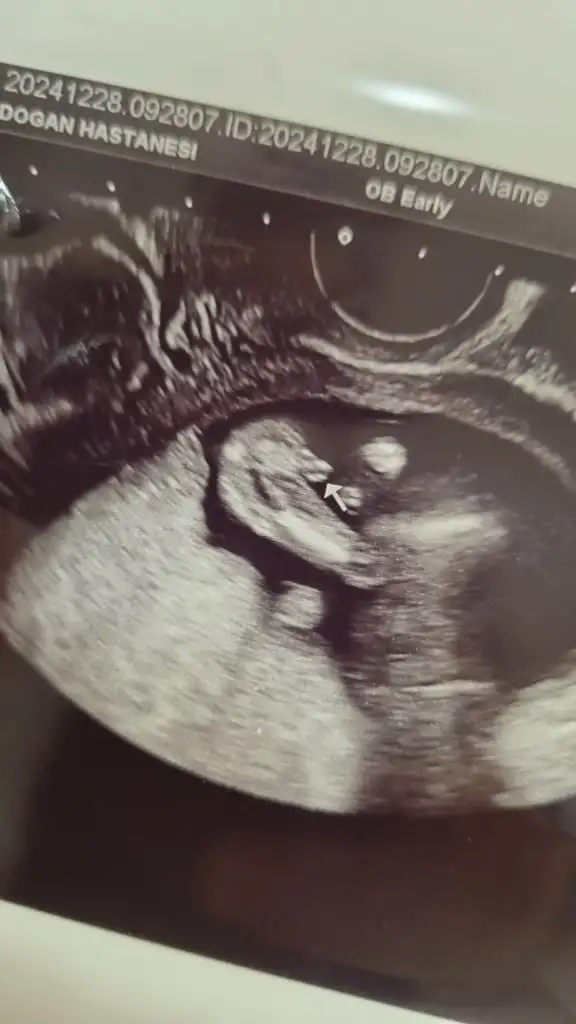

Buda 12+2 haftalık hala aynı fikirde misiniz acaba?Sizinki de erkek gibi görünüyor. Allah gönlünüze göre versin

Öbür ultrason fotoğrafında daha netti bunda emin olamadım. Doktor bir tahminde bulundu mu acabaBuda 12+2 haftalık hala aynı fikirde misiniz acaba?

Doktor hiç tahminde bulunmadı bir sonraki sefer dedi ve 15.haftada çağırdı tekrar ama dün Fetal dna yaptırdım zaten onda en geç 10 günde cinsiyeti çıkacakÖbür ultrason fotoğrafında daha netti bunda emin olamadım. Doktor bir tahminde bulundu mu acaba

Evet çıkıyor gönlünüzce olur umarımDoktor hiç tahminde bulunmadı bir sonraki sefer dedi ve 15.haftada çağırdı tekrar ama dün Fetal dna yaptırdım zaten onda en geç 10 günde cinsiyeti çıkacak